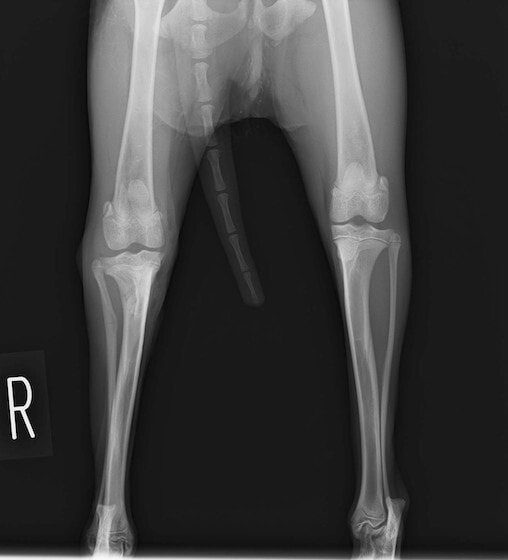

交通事故直後、胸腰部に激しい疼痛、両後肢に完全麻痺を認め、シェフシェリントン徴候を呈していました。レントゲン検査において、第11-12胸椎間の脱臼が認められました。

脊髄の減圧、脊柱管の再構築・安定化を目的に、片側椎弓切除術およびMatrixMANDIBLE Plateによる椎体固定を実施しました。

隣接椎体を架橋するようにプレートを設置しました。

術後レントゲン写真